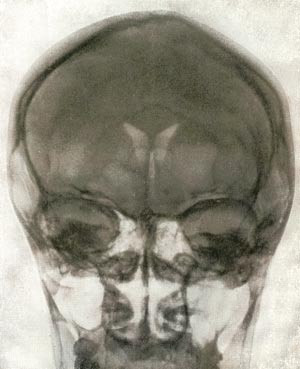

Sigvald B. Refsum var Monrad-Krohns etterfølger som professor i nevrologi ved Rikshospitalet. Den amerikanske nevrologen Harold Klawans har i sin bok Defending the cave woman beskrevet en episode fra Refsums besøk i USA i 1964 (9). Refsum gav da Klawans et eksemplar av boken The clinical examination of the central nervous system. Monrad-Krohns klassiske lærebok var dette året utkommet i 12. utgave (10). Refsum uttalte at det var meget viktig for Klawans å ha denne boken, fordi den inneholdt et bilde av et normalt pneumoencefalogram (fig 2) (10). Klawans svarte at det inneholder jo alle slike lærebøker. Refsum svarte da: «It’s Quisling’s. We had to make sure his aberrant behavior was not due to any neurological disease. We did a pneumoencephalogram of his brain. It was normal.» Klawans: «Then he was shot?» Refsum: «Yes.» Klawans: «Before or after his headache went away?» Refsum: «I never asked.»